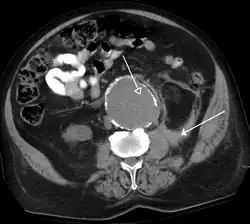

Non-contrast CT scans Figure 1a (left) and 1b (right) are of limited use for the differentiation of soft tissue structures. However, materials like blood, calcium (renal stones, vascular atherosclerosis), bone, and pulmonary parenchyma are highly visible and can usually be adequately assessed with non-contrast CT. For example, in the abdomen and pelvis, there are several indications for non-contrast imaging. These include: evaluation of renal calculi; assessment for gross intra-abdominal hemorrhage; and post-endostent volume measurements. In addition, non-contrast images are often obtained in conjunction with contrast enhanced images in evaluating potential renal transplant donors and in the evaluation of the pancreas (in combination with contrast phases). Of note, dual-energy CT and the development of virtual "non-contrast" images (VNC imaging) may ultimately obviate the combination scans. Additionally, CT angiography examinations performed for pathologies like aneurysms and dissection are frequently performed in conjunction with non-contrast imaging. The non-contrast images facilitate the differentiation of active extravasation or acute bleeding from vascular calcifications.